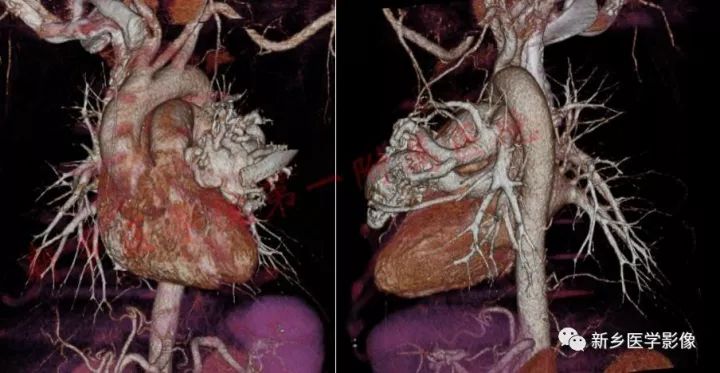

【病例】肺动脉静脉畸形1例CT

女,49岁

主诉: 间断发热1年余,再发4天。现病史:1年前受凉后出现发热,最高体温至37.8-38℃,多于午后出现。4天前感冒后再次出现发热,午后出现,热峰至38℃,伴双腿膝关节酸沉、乏力。

既往史:自诉有“先天性心脏病”30余年,当地医院诊断为“二尖瓣狭窄”,未给予诊治。诉“低血压”史,具体血压值不详。

查体:杵状指(趾)

肺动脉静脉畸形是指肺动脉与肺静脉直接相通形成的血流短路,是非常罕见的心脏外右向左分流性疾病。